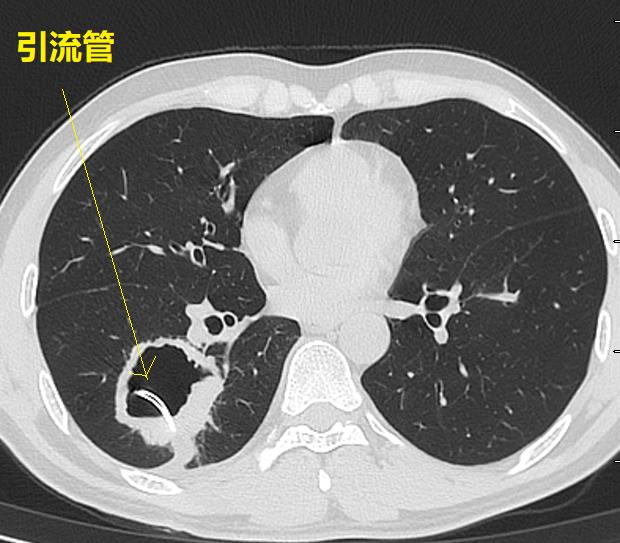

外院不知道为什么就考虑肺脓肿,还在“脓腔”里面放一大个引流管。这种骚操作,不容易见到。各位请看。

图02-05

首先,我们不得不承认,这个放引流管的水平,确实高!就像洲际导弹,准确的命中目标,引流管放在了空洞的正中央。

这个空洞,是个典型的肺鳞癌。根本就没有必要放个引流管。

首先,患者没有明显的感染症状!其次,这个空洞没有气液平,也不像肺脓肿。最后,这个空洞乱糟糟的,有些地方壁厚,有些地方壁薄,空洞里面凹凸不平,空洞周围边界清晰,没有炎症反应引起的模糊阴影。外加患者是中年人,基本上就是肺鳞癌。